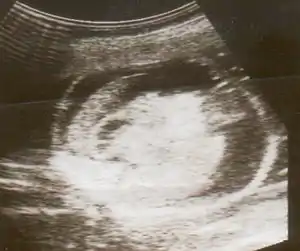

| An ultrasound showing a fetus with hydrops fetalis | |

Hydrops fetalis can be diagnosed and monitored by ultrasound scans.[1] An official diagnosis is made by identifying excess serous fluid in at least one space (ascites, pleural effusion, of pericardial effusion) accompanied by skin edema (greater than 5 mm thick). A diagnosis can also be made by identifying excess serous fluid in two potential spaces without accompanying edema. Prenatal ultrasound scanning enables early recognition of hydrops fetalis and has been enhanced with the introduction of MCA Doppler.[6]